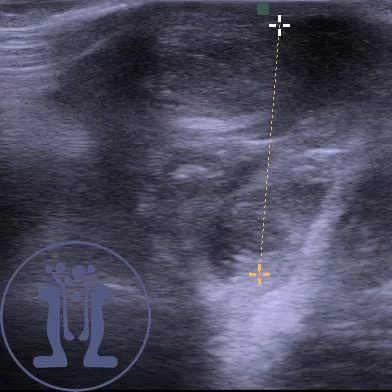

Το διαδερμικό και το ενδοπρωκτικό υπερηχογραφημα θα βοηθήσουν στην σωστή διάγνωση και διάκριση από άλλες παθήσεις όπως το απόστημα.

Επίσης θα ξεχωρίσουν τα περιστατικά στα οποία χρειάζεται επειγόντως διάνοιξη του θρόμβου.